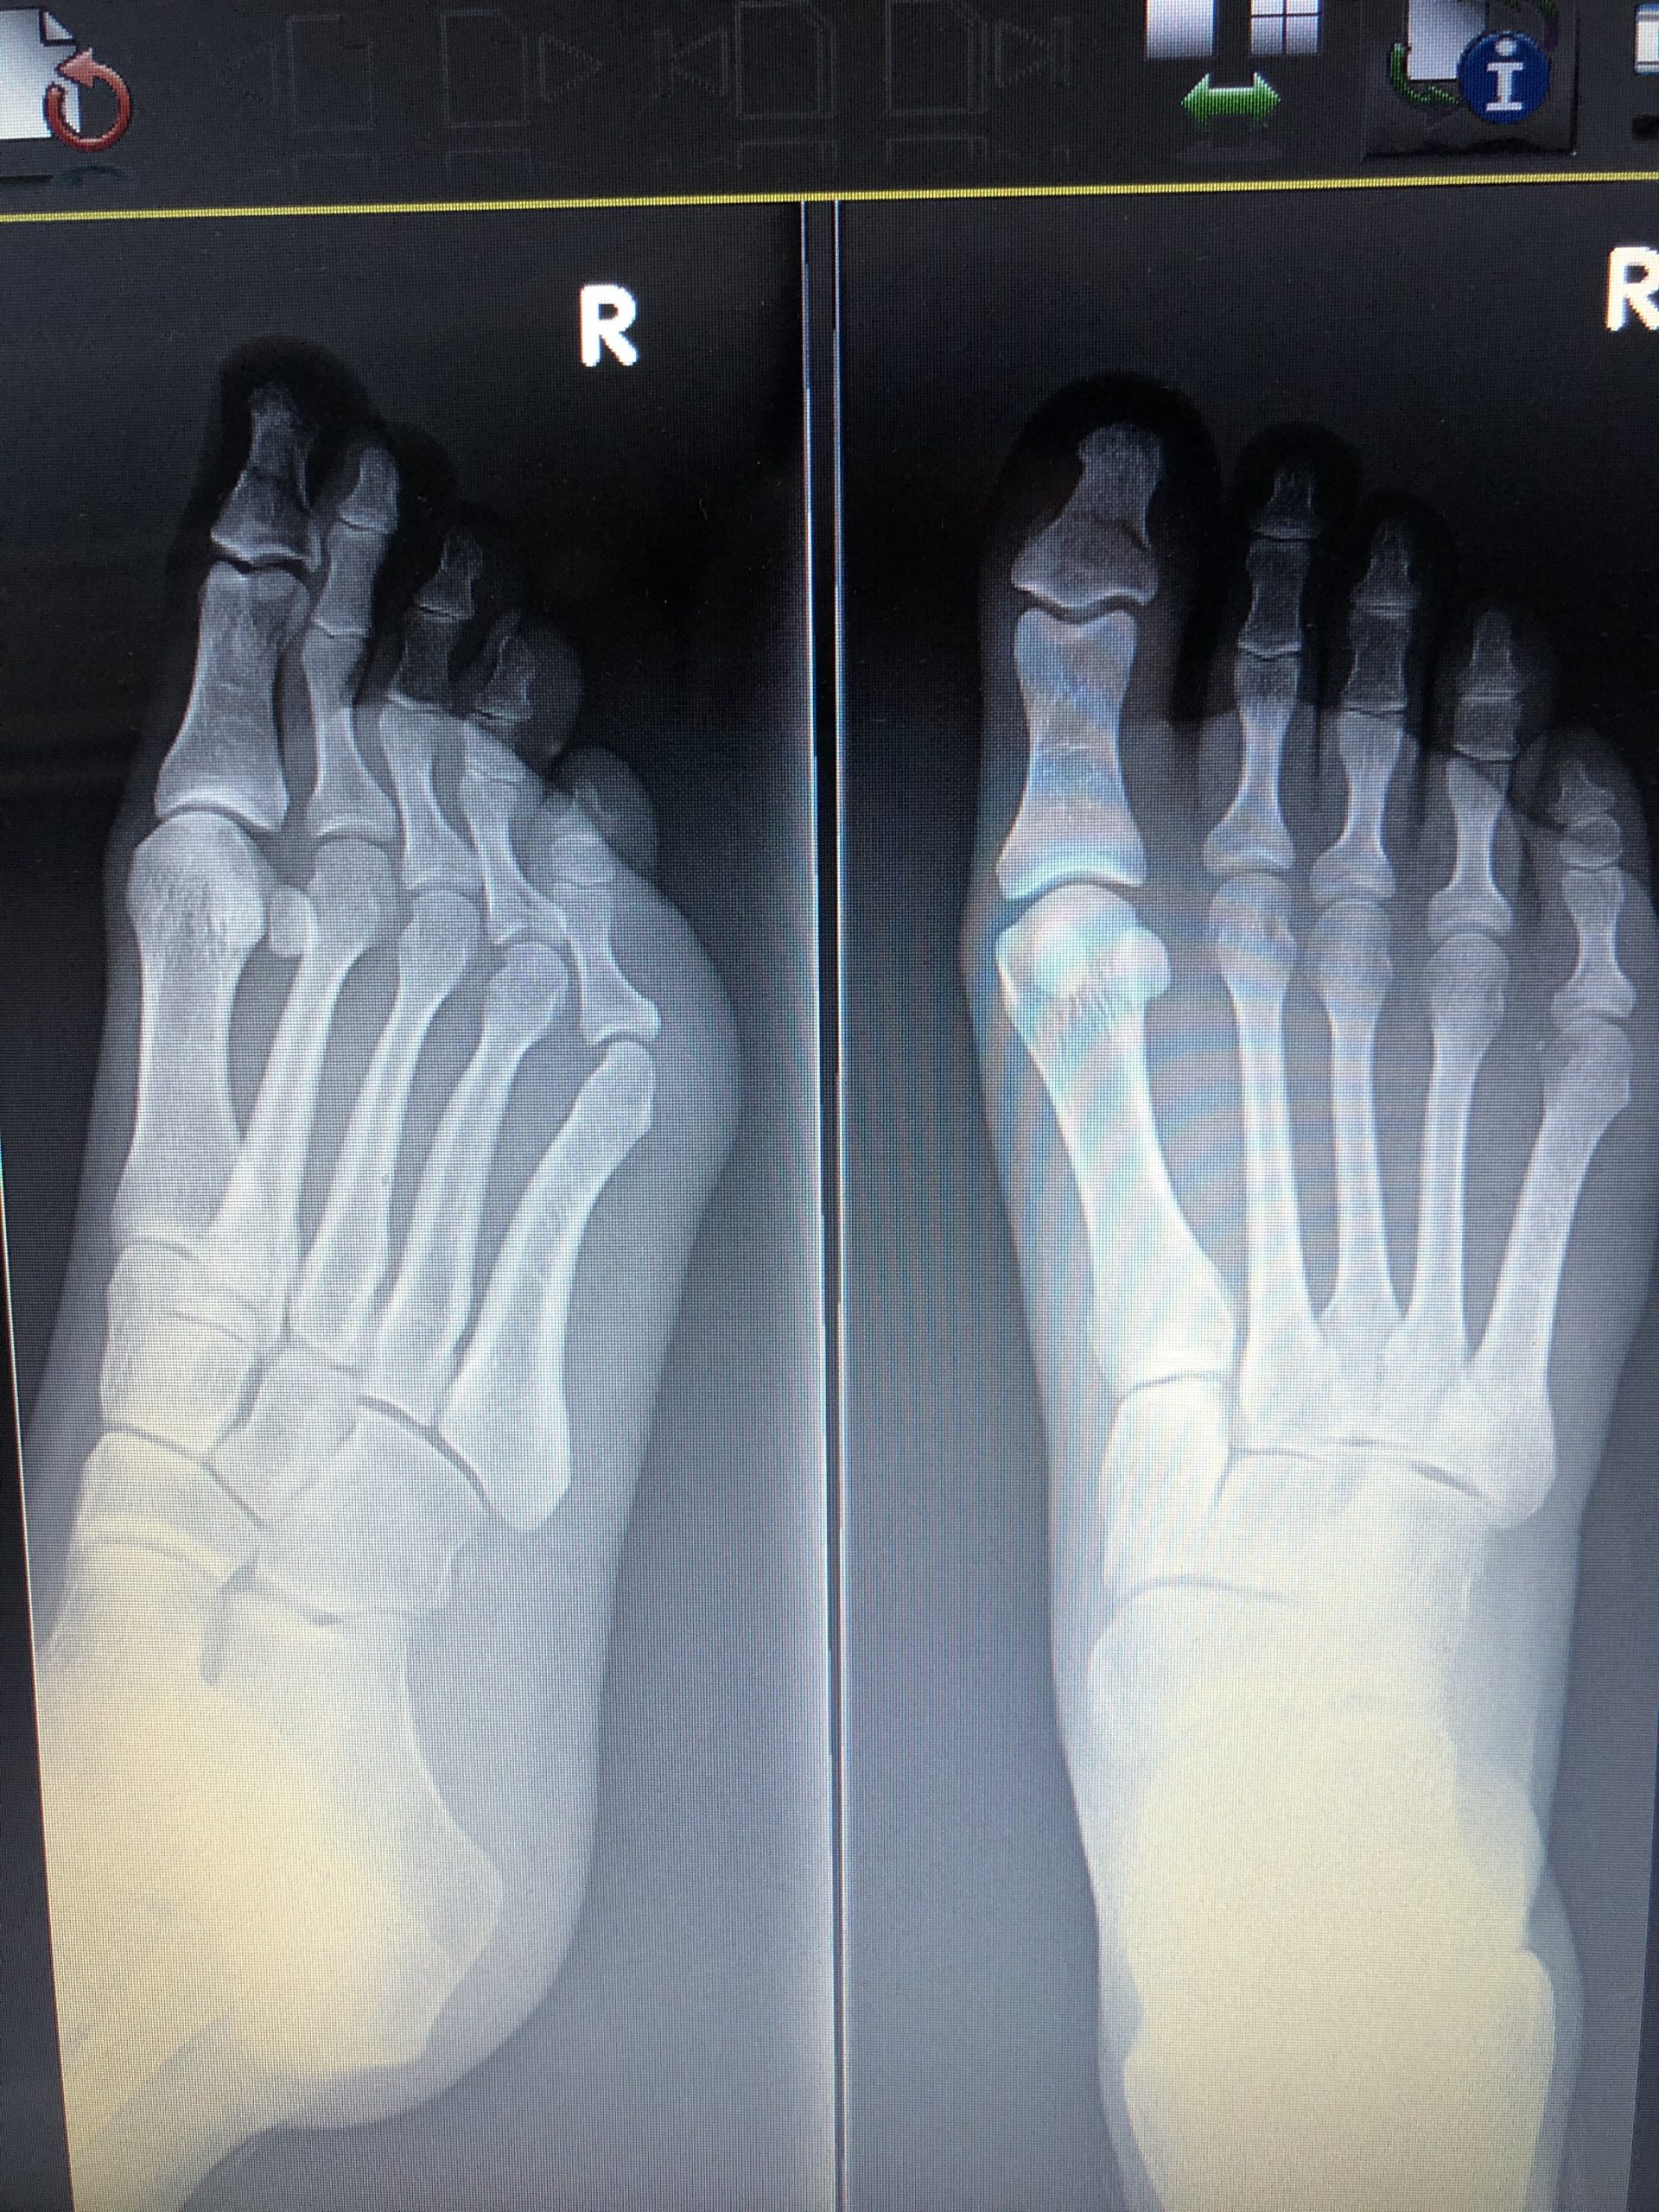

One of the most painful parts of this year was, without a doubt, when I broke my toe. Israel is not the best when it comes to patient care, especially when your insurance instructs you to go to a clinic for soldiers rather than the hospital! After getting an x-ray, the doctor squeezed a splint on my guillotined toe, giving me zero painkillers nor crutches and leaving me to cry my way out the door. I’m sure everyone in the waiting room turned to look at the closed door when I screamed at the pain of the splint being wrapped around my poor toe. Thankfully, I was able to get some crutches later on, and within three months, I was back to normal.